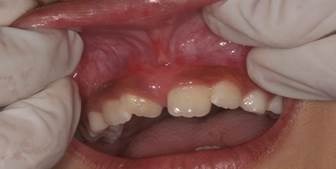

Figura 5: Fotografia realizada imediatamente após a cirurgia

Não houve necessidade de estabilização protetora e o procedimento ocorreu sem sangramento, dor e edema. Ao final, foi realizado um registro de imagem pós cirúrgico, repassadas orientações pós-operatórias e prescrito Paracetamol 200 mg em forma de suspensão, se necessário, de 6 em 6 horas.

Depois de 10 dias, a paciente retornou para reavaliação e apresentou cicatrização dentro do esperado. Não relatou nenhuma sintomatologia dolorosa ou outra queixa.

Figura 5: Sítio cirúrgico 10 dias após a frenectomia

Quando se completaram 24 dias da cirurgia, a criança retornou para consulta de acompanhamento com excelente cicatrização, sem cicatrizes e muito feliz. Após cicatrização completa, a paciente foi encaminhada para a ortodontia.

Figura 6: Sítio cirúrgico 24 dias após a cirurgia